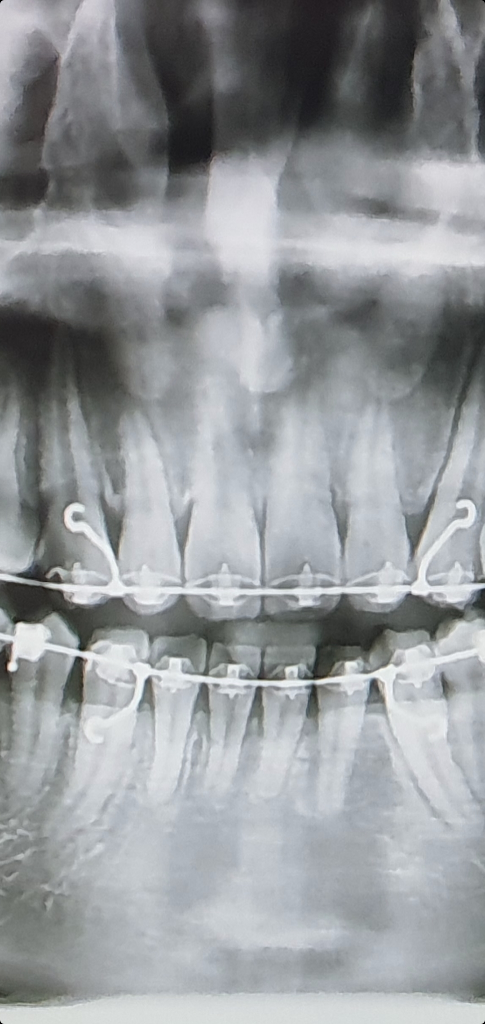

교정 후 사진입니다.

아래쪽 앞니가 특히 많이 휘었는데 교정치과에서는 괜찮다고 계속 진행해도 된다고 하네요.

이게 정상이 맞나요?

• 1번 째 사진

교정을 한다고 뿌리가 휘거나 그렇진 않습니다. 사진상 약간의 오류처럼 보입니다. 크게 문제가 잇어 보이진 않습니다.